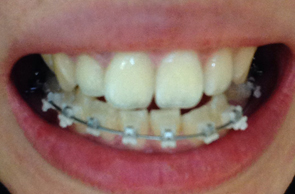

새로 갈아끼운 와이어는 2단계높인 와이어라고 설명해주셨어요 이 와이어는 입안 온도에서 더욱 효과가 잘 일어나는 와이어로 찬 온도에서 그 기능이 저하 될수 있기때문에 얼음물이나 차가운 음료는 많이 마시지 않는게 좋다고 말씀해주셨어요

그 설명을 듣는동안 우와 정말 와이어 하나에도 신기하고 대단한 기술들이 숨어있구나 하는 생각이 들었죠

와이어를 장치들 사이에 끼워넣고 탁탁 장치를 맞출때마다 치아가 하나씩 타이트하게 조이는 느낌이 들어왔어요 이때 어느분은 아프다고 느끼실수도 있겠지만 저는 뭔가 딱! 잡아주는 느낌같았어요 뭔가 배에 복대를 했으때의 느낌이랄까 ,,ㅋㅋ